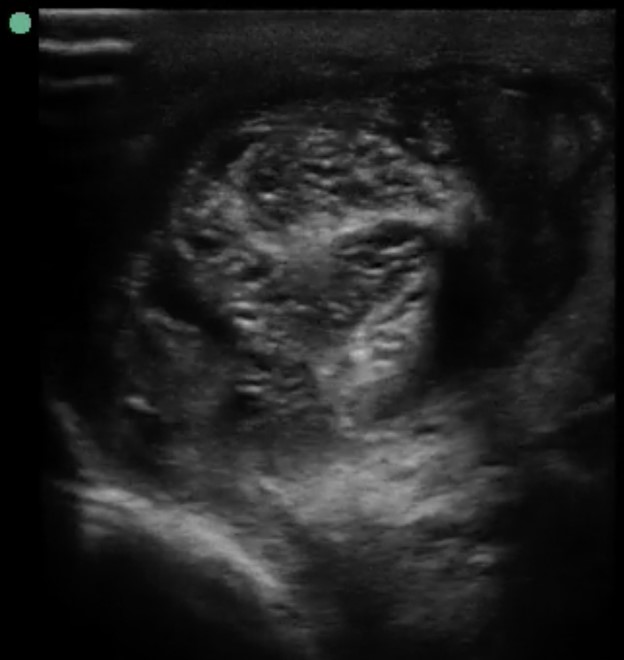

Bedside ultrasound was performed, and in the transverse view of the left testis, the subcutaneous tissues look thickened. There was obvious edema noted, and mixed echogenicity within the testis indicated possible necrosis. There were no signs of gas or cobblestoning; however, the epididymis appeared thickened.

Image 1. Left proximal transverse view shows the whirlpool sign in the left spermatic cord.

There are several signs of testicular torsion on scrotal ultrasound. Starting from the superior aspect, the spermatic cord can be seen with a whirlpool sign (knot-like) when compared to the unaffected side. This sign has high specificity with low sensitivity in Baud et al.,8 from 1998 and again demonstrated in McDowall’s meta-analysis in 2018.4 For now, the sign rules in testicular torsion but does not rule it out. Several other signs will favor the diagnosis, such as: spiral-like flow on color Doppler, an up-tracking epididymis as it is being dragged towards the inguinal canal, or an increased testicular size compared to a normal contralateral testis.

The high-frequency probe (at least 7.5 MHz) should be used to evaluate the testicle. Ideally, the patient should be supine, knees bent with the hips externally rotated (frog leg position). The unaffected side should be scanned first in order to establish a baseline. Fully scan each testis, epididymis, and spermatic cord in both the longitudinal and transverse planes, starting medially and moving laterally. The portion of spermatic cord superior to the epididymis is where the whirlpool sign can be seen. It is imperative to obtain the view that includes both testes in order to evaluate for asymmetry, which is known as the “Buddy View.” Finally, color or power Doppler (the latter is more sensitive in low flow states but cannot differentiate direction) can evaluate for the presence or absence of blood flow to each testicle.11 The Doppler mode of choice should be power Doppler (which is up to 5 times more sensitive than color Doppler) to detect the “slow-moving” blood in the testes [10]. In case of ongoing torsion, the affected testicle will appear hypoechoic compared to the unaffected side as a result of edema and eventual necrosis.10